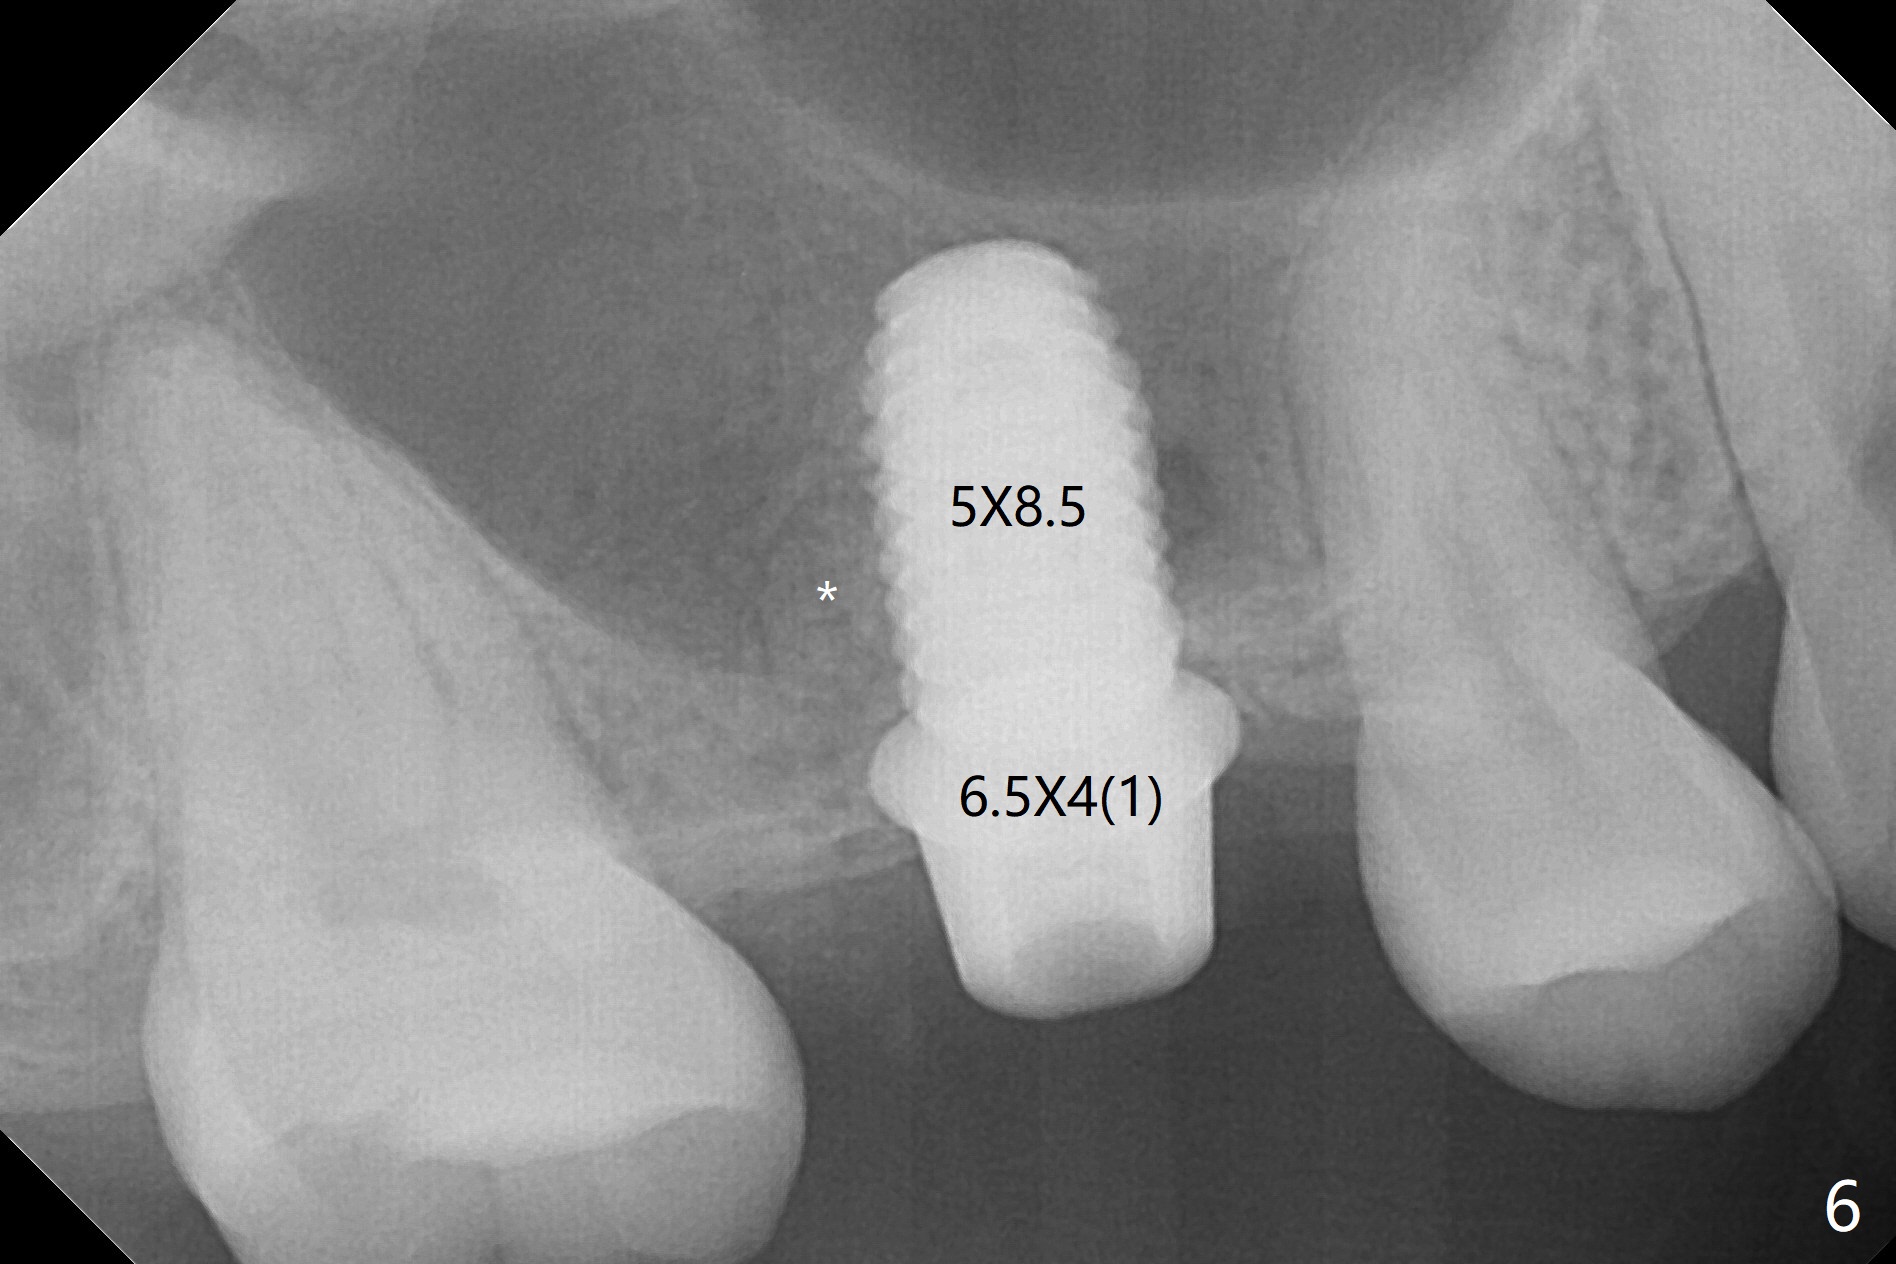

When the residual roots of the tooth #3 are removed, there is a gingival band over the septum (Fig.1 S). Osteotomy (Fig.2 yellow circle) would tear it off. To save the soft tissue, the buccal attachment is severed (Fig.3 black line), the flap is rotated palatal (Fig.3 curved arrow) and sutured in place (Fig.5 S). After sinus floor breakdown (use of sinus drill for 16 mm) and use of membrane lifter/water, two pieces of PRF membrane are inserted. The membrane is so slippery that it is easy to enter the sinus for further sinus membrane lift and later allograft placement (Fig.4 *). A 4.5x10 mm dummy implant is placed with high torque after 4x7.3 mm drill with 3 mm stopper so that 4.5x7.3 mm drill with 1 mm stopper is used before placement of a 5x8.5 mm final implant with ~ 35 Ncm (Fig.5-7). The patient reports anterior sinus wall tenderness with right nasal discharge a few days postop. The provisional has mobility without tenderness 1 week postop. It appears that the sinus membrane has been involved, which is quickly repaired probably by PRF. There is no pain when a 5.2x4(2) mm cemented abutment is torqued at 30-35 Ncm before impression (Fig.8). The surrounding soft tissue is healthy. When the permanent crown is delivered, the patient feels light pain when she bites hard. The discomfort persists 4 months post cementation (Fig.9). The crown/abutment is replaced with a healing abutment (Fig.10). There is no bone loss 4 months post healing abutment placement (14 months post implant placement, Fig.11). Upper Molar Immediate Implant, Prevent Molar Periimplantitis (Protocols, Table), Trajectory II, 31 Flap Not Transferred Xin Wei, DDS, PhD, MS 1st edition 07/26/2019, last revision 10/05/2020